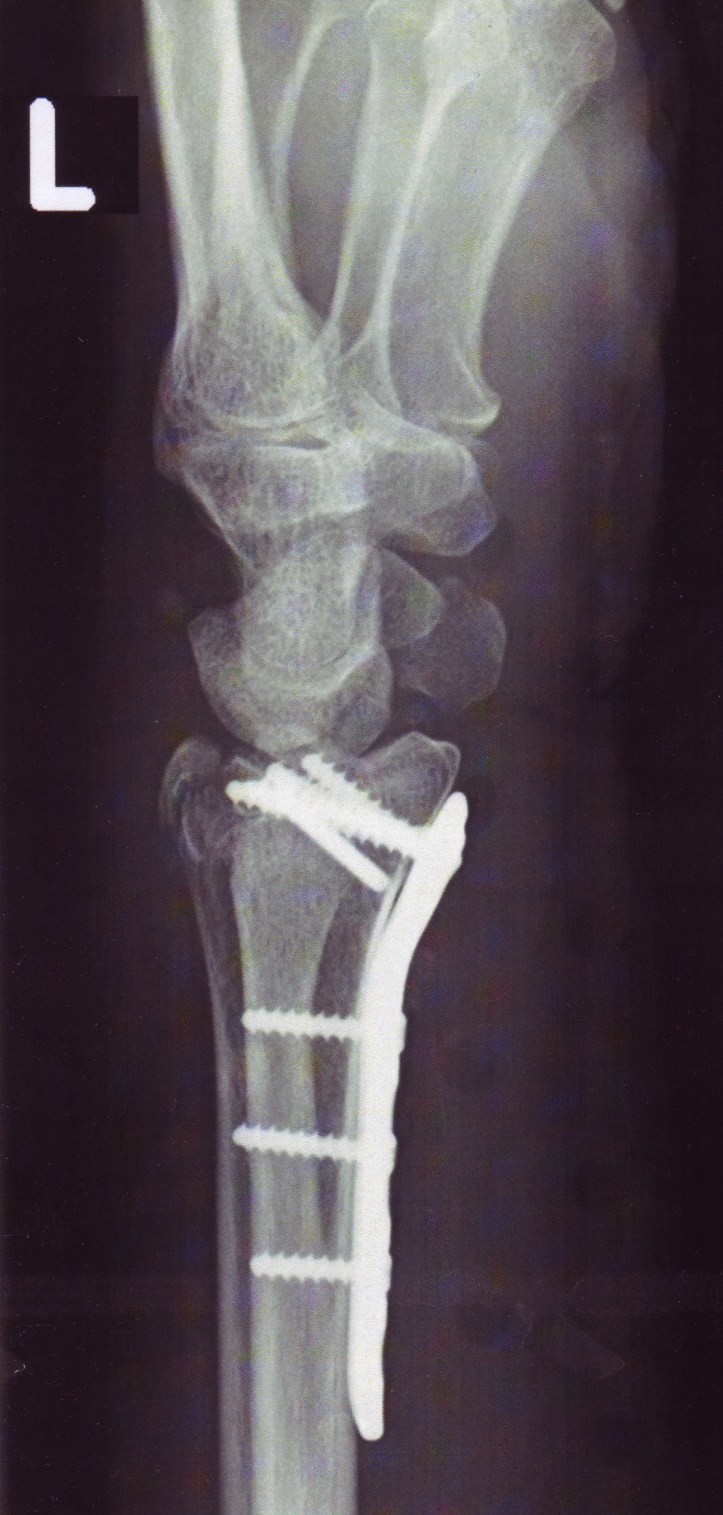

Der kaputte Flügel wird so langsam wieder. Ich bin zugekleistert mit Terminen Krankengymnastik, Röntgen, Verbandwechsel… Freitag werden die Fäden gezogen. Und dann kam auch noch die Röntgenklinik auf die Idee, dass sie die ersten Aufnahmen aus Merheim haben wollten. Also bin ich nach Mehrheit gelatscht, habe meine Fotos durch drei Abteilungen verfolgt…und als ich dann in Kalk damit ankam, wollte sie niemand sehen und CDs dürfen sie sowieso nicht einlesen wegen Virengefahr.